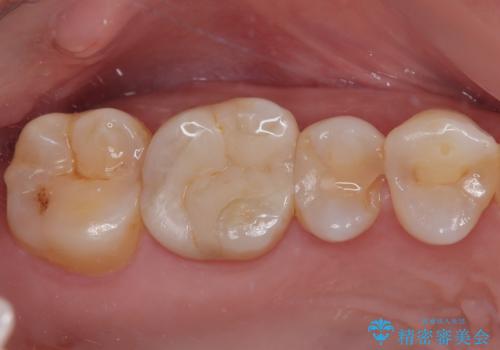

- 今回は、「右上の詰め物が欠けてしまった」という主訴で来院された、40代女性の患者さんの症例をご紹介します。

診察の結果、上顎右側第二小臼歯に装着されていた詰め物の一部が欠けている状態でした。一見すると小さな欠けに見えますが、詰め物が破損した部分はプラーク(歯垢)が非常に溜まりやすく、虫歯の再発リスクが高い状態になります。